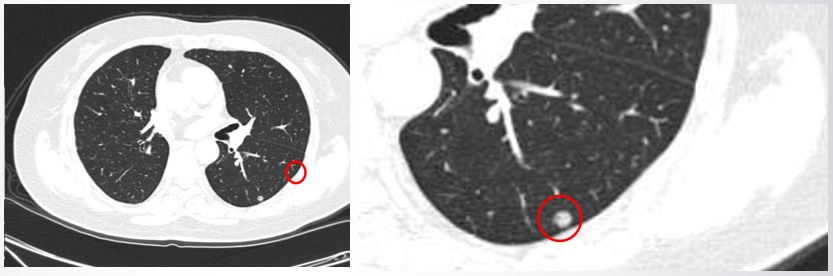

患者胸部CT

2017年3月胸部CT提示左肺下叶背段有一密度增高的结节,直径为7 mm。结合患者信息和影像学表现,我们判断为孤立性肺结节。

1月23日CT结果提示左肺下叶后基底段胸膜下可见一结节肺结节10个人9个人有吗,直径约为12 mm,增强后有较明显强化,边界欠清楚,周围可见散在多发小结节状、片状致密实变影伴片状渗出,病变边缘模糊,邻近胸膜略牵拉、增厚。另外病变周围可见条索状稍高密度影,边缘锐利。双肺胸膜下散在细条索、结节状高密影,边界清楚,部分见钙化影。